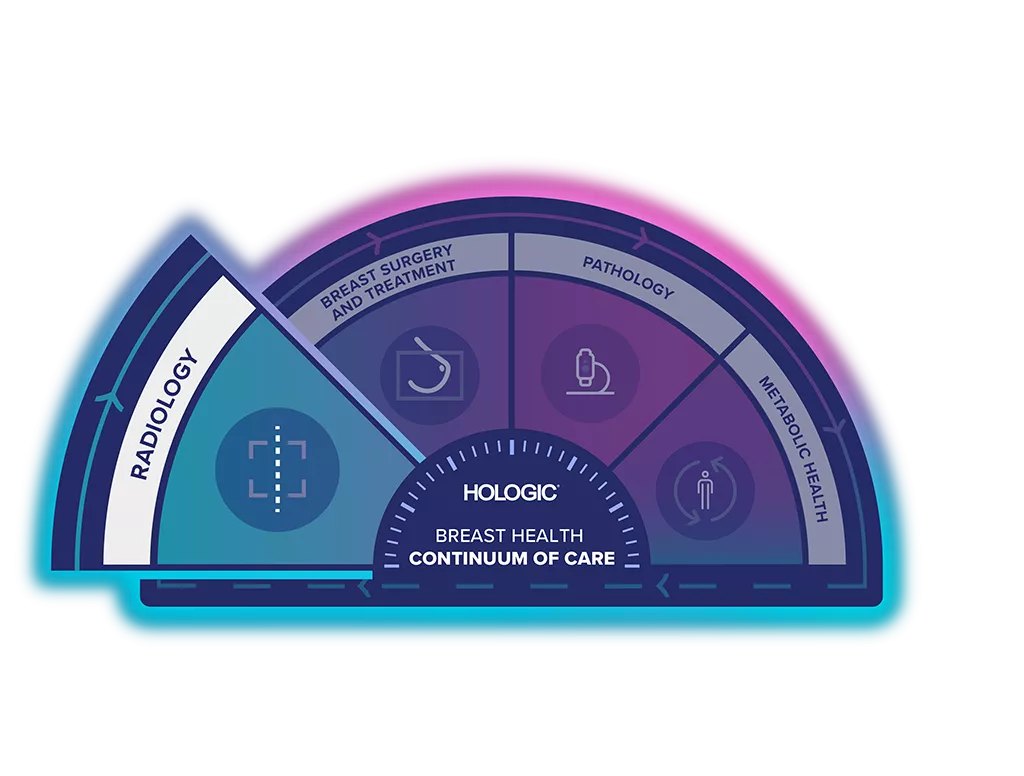

The Breast Health Continuum of Care offers integrated solutions for clinical confidence, workflow efficiency and compassionate patient care. It is our purpose to give more women more time in better health.

The Breast Biopsy Site Marker range is part of the Hologic Localisation and Marking Solution.